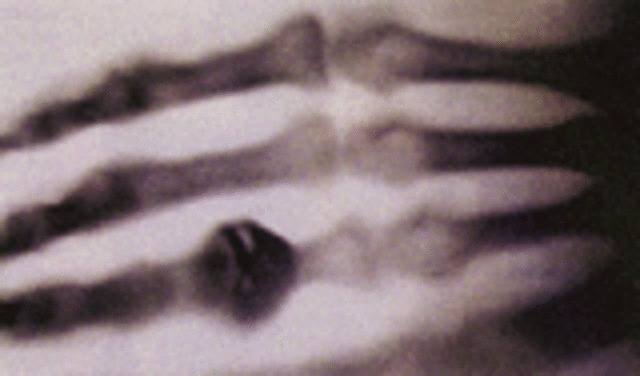

• X-Ray

X-Ray

Willhelm Conrad Rontgen invented the X-Ray, which intiated the use of X-Rays in hospitals. Now, medical areas all around the world use X-Rays for numerous uses.